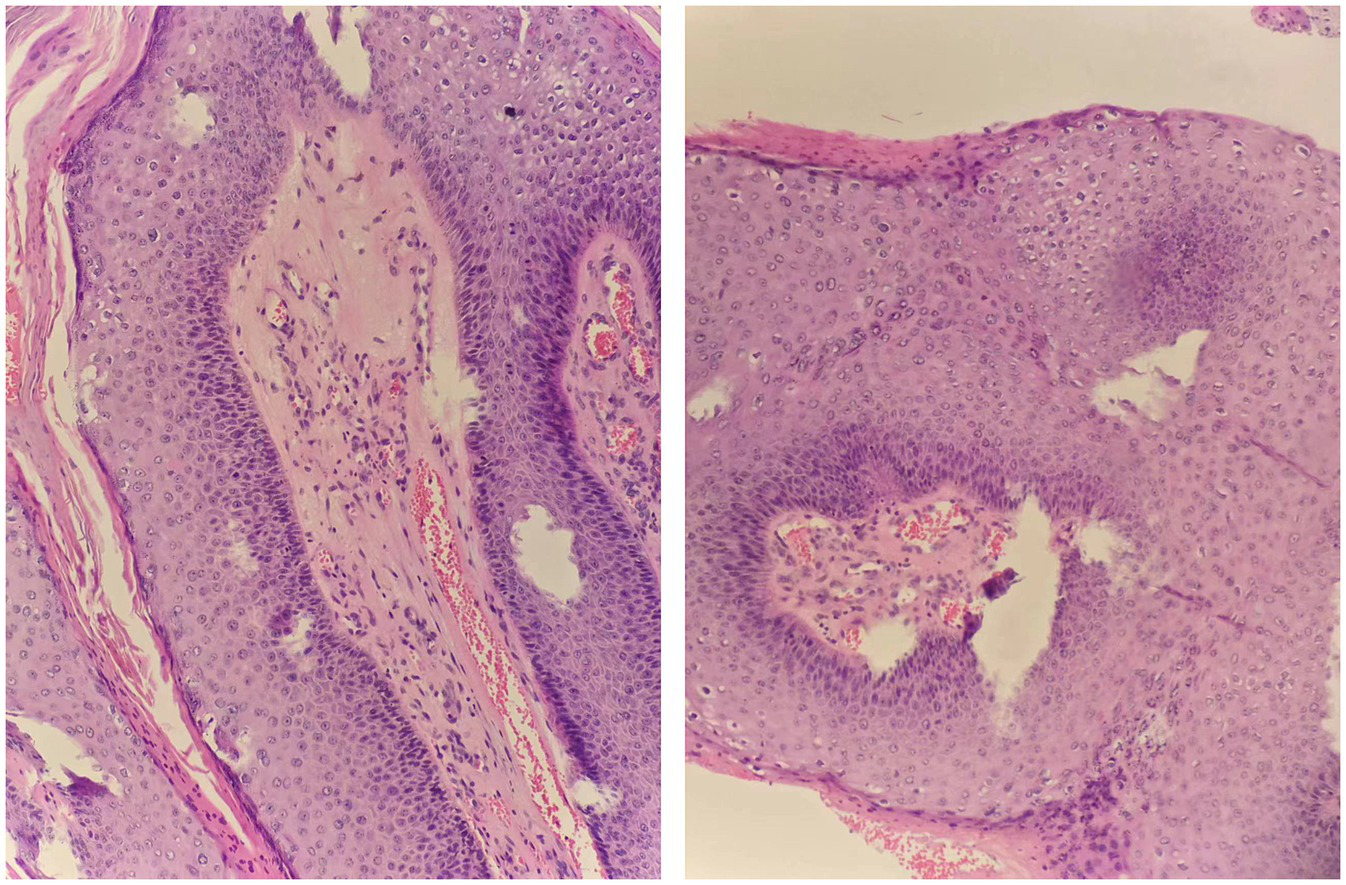

Figure 2

Pathological examination of scrotal and penile skin lesions (HE staining, 40×).

A 33-year-old male presented to us with a 10-year history of plaque psoriasis which worsened 15 months ago. Lesions appeared on the head, trunk, limbs, and scrotum. He was initially treated with oral Acitretin capsules 30 mg/d and topical clobetasol propionate cream for 1 month, but the effect was unsatisfactory, and the skin lesions continued to worsen. After excluding contraindications such as malignant tumors and infection, the patient was treated with secukinumab. Nine months ago, multiple sesame seed-sized brown papules appeared on the original skin lesion of the scrotum, which were initially asymptomatic. Within 1 month, the skin lesions rapidly enlarged and merged into patches, and similar lesions also appeared on the penis, acquiring a wart-like appearance and emitting a foul odor. Physical examination showed a brown patch of approximately 6.0 × 4.0 × 0.5 cm on the scrotum, consisting of numerous pedunculated vegetations with a wart-like appearance, and multiple similar lesions could be seen on the penis. Multiple pale red patches were also present on the scrotum, with a few scales on the surface (Figure 1). HPV-DNA examination confirmed the presence of HPV11, and serological examination showed no HIV infection. Pathology results revealed excessive keratinization and incomplete keratinization, hypertrophic spinous layers, and papillomatous hyperplasia, consistent with the diagnosis of condyloma acuminatum; the tumor cells show no atypia and they do not exhibit invasive growth, thus ruling out the possibility of Buschke-Löwenstein tumor (Figure 2). This patient was finally diagnosed with condyloma acuminatum. Considering that the patient has been treated with secukinumab and the condyloma acuminatum rapidly increase within one month, we strongly suspect that the onset and progression of condyloma acuminatum are related to the use of secukinumab. Considering the large size of the skin lesions and the patient’s own need for rapid removal of the lesions, we perform surgery to gradually remove the skin lesions using cutting and electrocautery techniques. The patient continued to receive secukinumab after sugery. During the 8-month follow-up period, there was no recurrence of condyloma acuminatum (Figure 3). The patient is very satisfied with our treatment.